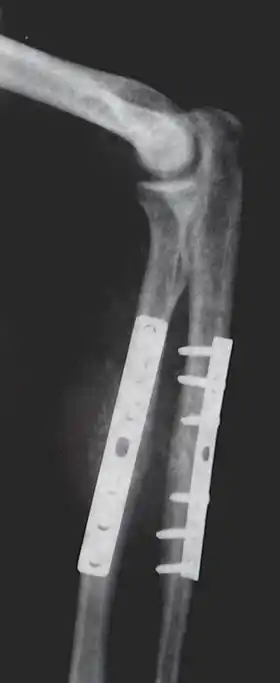

Closed Reduction Internal Fixation (CRIF) is reduction without any open surgery, followed by internal fixation. It appears to be an acceptable alternative in unstable distressed lateral condylar fractures of the humerus in children, but if fracture displacement after closed reduction exceeds 2 mm, open reduction and internal fixation is recommended.[4]

Various techniques of minimally invasive surgery for internal fixation of bones have been reported. The treatment of fractures of the distal third of the tibia has evolved with the development of improved imaging and surgical techniques.[5]

Additional images